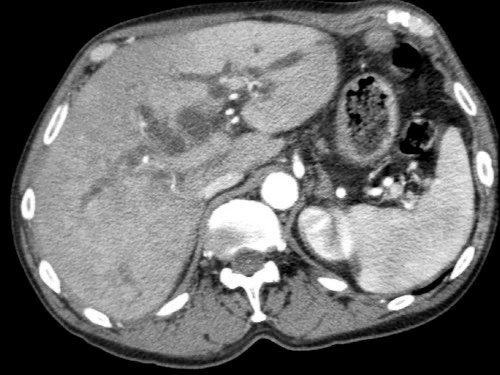

CT axial cho thấy:

- Khối u ở thân tụy (đầu mũi tên trắng).

- Tiếp xúc khu trú < 90º với động mạch mạc treo tràng trên (SMA).

- Tiếp xúc rộng hơn từ 90º – 180º với SMV, SMV bị hẹp nhẹ và biến dạng (mũi tên vàng).

- Giãn ống tụy